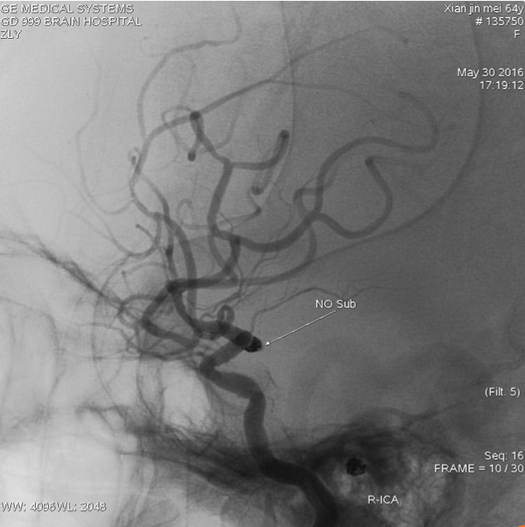

栓塞后不减影,弹簧圈形态符合动脉瘤形态

支架完全打开,与血管贴壁良好,覆盖瘤颈口满意